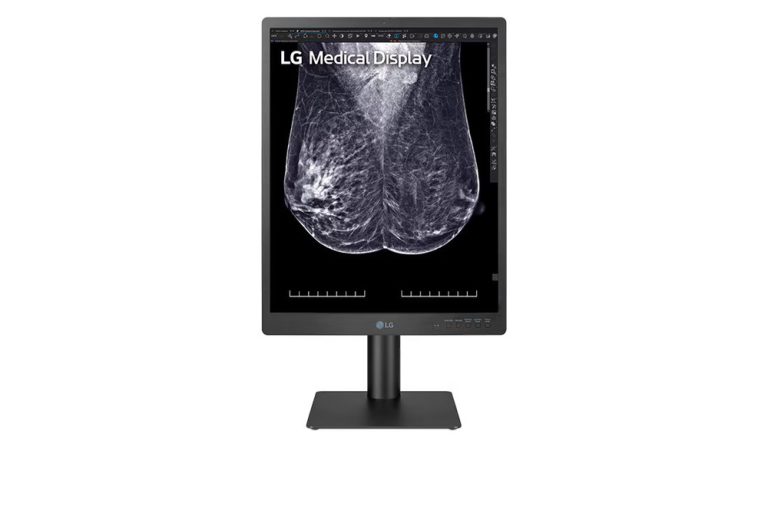

LG 21HQ613D-B – 21″ 5MP Diagnostic Medical Monitor

SKU:

21HQ613D-B

LG 24HR513C-B – 24″ 2MP Diagnostic Medical Monitor

SKU:

24HR513C-B